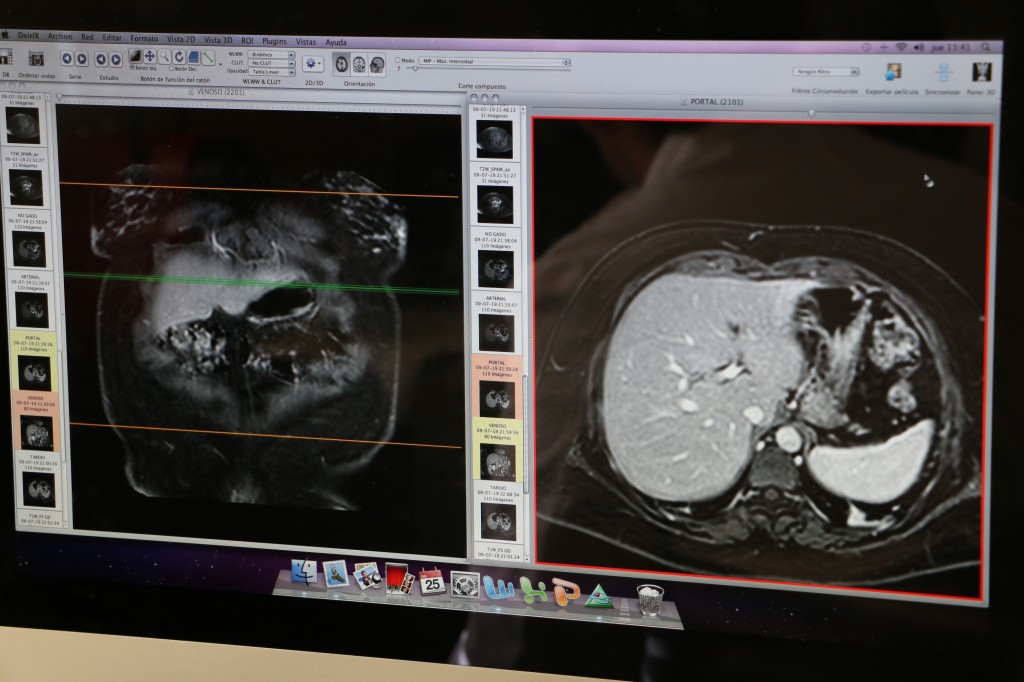

El resonador de 1.5 teslas de potencia en su campo magnético, cuenta con la más alta tecnología para realizar todo tipo de exámenes, como destaca el Dr. Iván Vial, Jefe de la Unidad de Imagenología del centro asistencial, “El equipo se compró con las bobinas y software necesarios para realizar los estudios no sólo neurológicos y traumatológicos, que es lo más común, sino también estudios cardiológicos, de patología mamaria y de abdomen, dedicados a ciertas estructuras y patologías, principalmente funcionales cardiacas y patología oncológica. Al margen de hacer todos los exámenes que se pueden realizar con un equipo como éste: de cerebro, columna y articulaciones”, indicó el especialista.

Martín Acevedo tecnólogo médico de resonancia en la Unidad de Imagenología del Hospital Dr. Gustavo Fricke SSVQ, expresa orgullo por el salto de calidad que dará el servicio en general al contar con este moderno equipo y explica cómo será la toma de exámenes a los pacientes, “Nosotros acá obtenemos imágenes del interior del cuerpo a través de un campo magnético potente, excitamos las moléculas de hidrógeno en todos los tejidos, para leerlos y traducirlos en imágenes en blanco y negro. Estoy muy motivado de seguir aprendiendo y también ayudando a la mayor cantidad de gente” detalló.